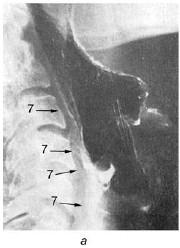

В боковой проекции отчетливо видны надгортанник, щитовидный и перстневидный хрящи, хуже визуализируется область черпаловидных хрящей. Для улучшения обозримости гортани и отдаления задней стенки ее от тел шейных позвонков обследуемому в момент экспозиции предлагают закрыть нос и сильно подуть в него (наподобие опыта Вальсальвы). Раздувание надгортанного пространства и гортаноглотки приводит к более отчетливому проявлению краев надгортанника, области черпаловидных хрящей и желудочков гортани.

Рис. 19.15. Схематическое изображение опознавательных признаков гортани в боковой (а) и прямой (б) проекциях (по Земцову Г. В., 1958). Объяснения в тексте

Рис. 19.17. Рентгенограмма гортани в боковой проекции с использованием рентгеноконтрастного вещества (а) и схематическое изображение ее опознавательных признаков (б); рентгенограмма гортани с напылением в прямой проекции (в) (по Pana I., 1973): 1 – ротоглотка; 2 – гортаноглотка; 3 – надскладочное пространство (rimavestibuli); 4 – подскладочное пространство (cavum inragloticum seu regio infraglotica); 5 – межскладочное пространство (rima glotidis); 6 – трахея; 7 – контуры гортани, визуализированные аэрозольным напылением контрастного вещества;